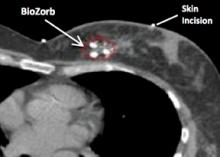

The trend in breast cancer treatment these days is all about precision, with the twin goals of controlling the cancer better and reducing side effects. Great advances have been made in radiation delivery methods that make it possible to more precisely target the tumor bed, plus a small margin around it where the cancer would be most likely to recur. By tightly focusing on these areas alone, radiation oncologists can minimize exposure to critical healthy tissue and structures such as the heart and lungs. Less damage to healthy tissue also means better cosmetic outcomes.